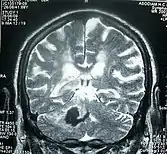

Perinatal stroke can be diagnosed with medical imaging techniques that present the brain's image. The usage of diffusion-weighted imaging with magnetic resonance imaging is effective for early diagnosis of perinatal stroke.[18] Computerized tomography (CT) is also a commonly used diagnostic technique for this disease.[37] These medical imaging techniques can show bleeding or blockage in the brain and detect damage caused by ischemic stroke or hemorrhages to the brain tissues.[38] Magnetic resonance imaging is clinically preferred to computerized tomography as it can highlight the brain's blood flow.[37] In addition, perinatal stroke is challenging to classify on computerized tomography as the neonatal brain has higher water content.[7][38] However, in certain situations, such as the inability to transport unstable infants with severe respiratory or cardiac disorders from the intensive care unit, cranial ultrasound is used as an alternative to magnetic resonance imaging.[7] Cranial ultrasound can identify intracranial hemorrhage, intraventricular hemorrhage, large cerebral sinus venous thrombosis along with the brain's blood flow.[7]